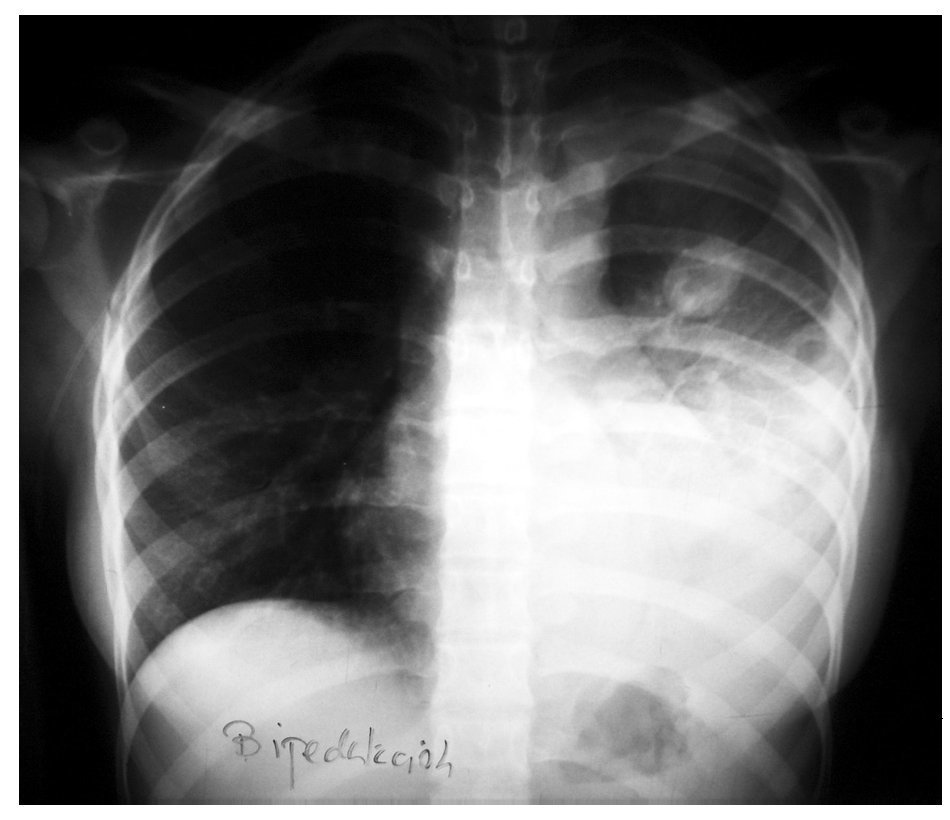

Fig. 1. Radiografía posteroanterior de tórax.

Se realizaron pruebas de imagen consistentes en radiografía simple de tórax y senos paranasales, tomografía computarizada de tórax, ecografía abdominal y ecografía doppler cervical.